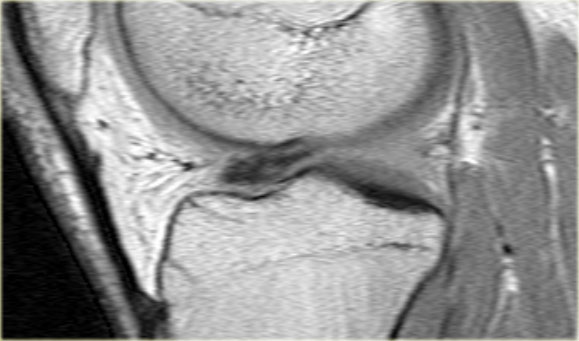

Bên trái là một trường hợp khác của sụn chêm ngoài bị lật.

- Lưu ý sừng trước rất lớn.

Phần trong là sừng sau đã bị di lệch. - Phần trong chạy vào hố gian lồi cầu.

- Phần bị di lệch được nhìn thấy rõ ràng như là ‘cấu trúc thứ ba’

trong hố gian lồi cầu. - Điểm nối với phần còn lại của sừng sau.

- Điểm nối với phần còn lại của sừng sau.

- Phần còn lại rất nhỏ của sừng sau.